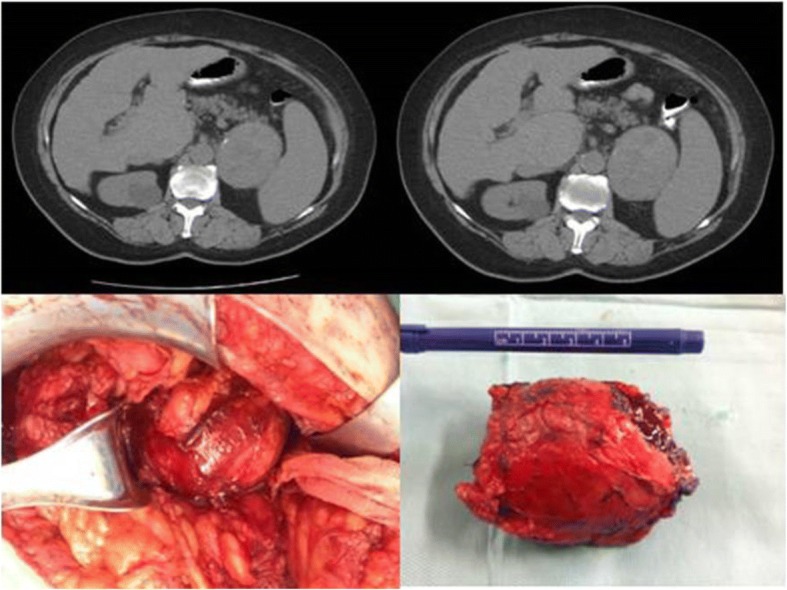

Fig. 2.

Intraoperative image of giant adrenocortical carcinoma with displacement of right hepatic lobe to the left and vena cava close to the anterior abdominal wall

A metastatic work-up included CT scans of her head and chest and a bone scan and they were negative for metastases. During laparotomy the giant tumor was removed completely with its own capsule, without the need for excision of adherent organs as there were no infiltrations.

Postoperative pathology results confirmed the diagnosis of ACC and no further adjuvant treatment was applied to our patient (Fig. 3). Her postoperative course has been uneventful for 1.5 years.

Laboratory testing revealed results that are shown in Table 2. A CT scan revealed a large invasive mass in the anatomical area of her left adrenal gland, well circumscribed, measuring 7 × 7 × 9 cm; it extended to the upper pole of her left kidney and the inner hilum of her spleen without infiltration of the above organs, which showed marked heterogeneous enhancement after intravenous infusion of a contrast agent, which posed a differential diagnosis problem with possible pheochromocytoma (Fig. 4).

Fig. 4.

Computed tomography and intraoperative findings of left adrenal pseudocyst

Further laboratory testing of post-prandial plasma cortisol and plasma testosterone levels gave normal results, mimicking a nonfunctional left ACC. Elective open adrenalectomy was scheduled without any complications and the postoperative pathology record was consistent with a pseudocyst, without evidence of malignancy (Figs. 4 and 5). She has had an uneventful course 1 year postoperatively.